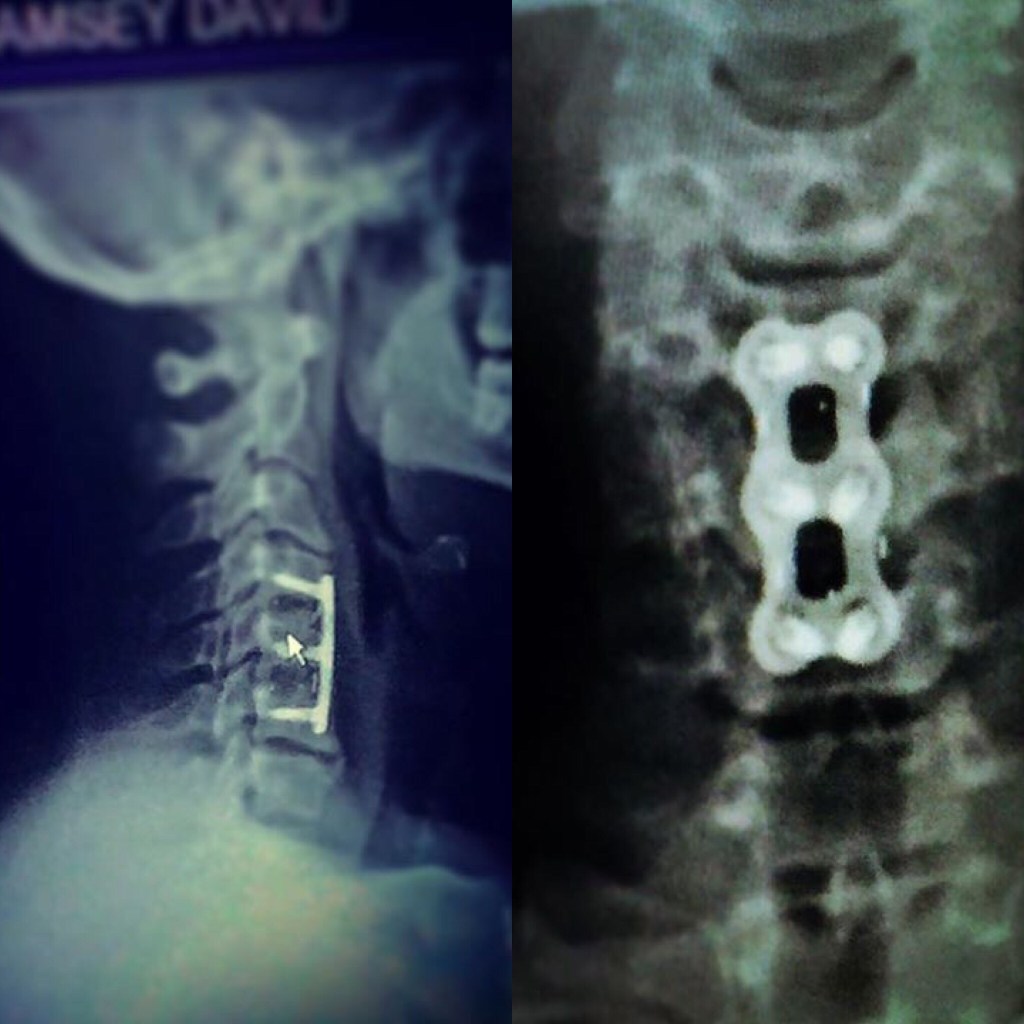

share #love #help #like #drugsaddiction #alcoholaddiction #drugabuse #alcoholabuse I’ve been #pillfree 3.5 yrs #cannabisfree over two years #alcoholfree 14months #hempfree 11mnths after 10 major surgeries 26 Prescriptions and 20 years military service im thankful I’m alive cervical fusion 3 lumbar fusions (fully fused now) both shoulders rebuilt both wrists and right knee. Still have numerous Herniations in neck and back and fractured vertebrae that healed wrong but the 100’s of 1000’s of lives saved was worth it! Now I’m sober and pray my children and I and my loved ones will reap this blessing because I truly have become better in life and it was worth it amen 🙏🏾 trust me! I’m sober

I am thankful for my children my three girls and son. And the legacy I will leave them. I’m thankful I’m sober! After 26 prescriptions, Cervical fusion, 3 lumbar fusions, both shoulders rebuilt, both wrists, right knee, three years acupuncture, years of therapy physical & mental, years of facing anxiety depression insomnia ptsd, drinking (socially) and yes as prescribed pill use! As well as two years cannabis 1.5 yrs HEMP I’m #sober #military #life #surfman374 #truelovefeelings #loveislove #GODIsLove #dmramsey1 on Twitter Surfman374 TilTok YouTube. From 2004 to date I’m posted my journey online that a lot of years in the #metaverse lmfao 🤣 #reapwhatyousow #Texas wish you believed in me! Because from 2011 to 2018 I served this state nation and nations! From 1998-2018 #MilitaryLife cost me everything! But I #NeverGiveUp and will not!